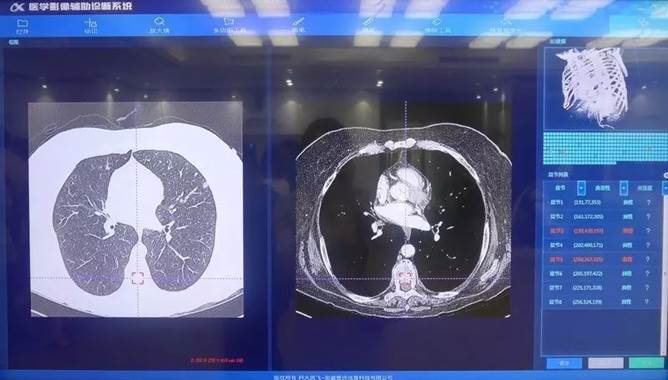

在医疗和教育这两大沉点民生领域������,科大讯飞在践行用人为智能建设美好世界�����?拼笱斗捎胄鸵窖г汉椭泄窖Э蒲г汉献������,通过对医疗影像大数据的深度进建������,实现分析医生和患者的互换实时天生电子病历、判断肺部结节的良性恶性和地位������,辅助医生诊断��。提升医生看诊效能的同时但愿能够最终解决中国全科医生稀缺的问题��。

科大讯飞医疗影像辅助诊断系统